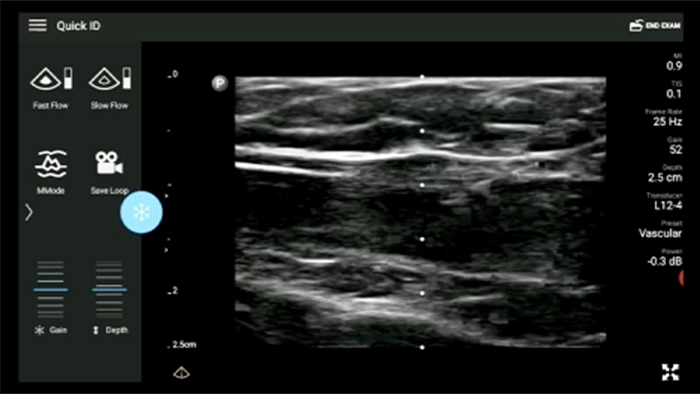

Decrease complications of CVC insertions

Real-time ultrasound guidance can improve the accuracy and safety of CVC insertions.

Lumify L12-4 broadband linear array transducer

• 12 to 4 MHz extended operating frequency range • Aperture size: 34mm • 2D, steerable color Doppler, M-mode, advanced XRES and multivariate harmonic imaging, SonoCT • High resolution imaging for shallow applications: soft tissue, vascular, superficial, musculoskeletal, and lung • Center line marker • USB-C transducer with replaceable cable